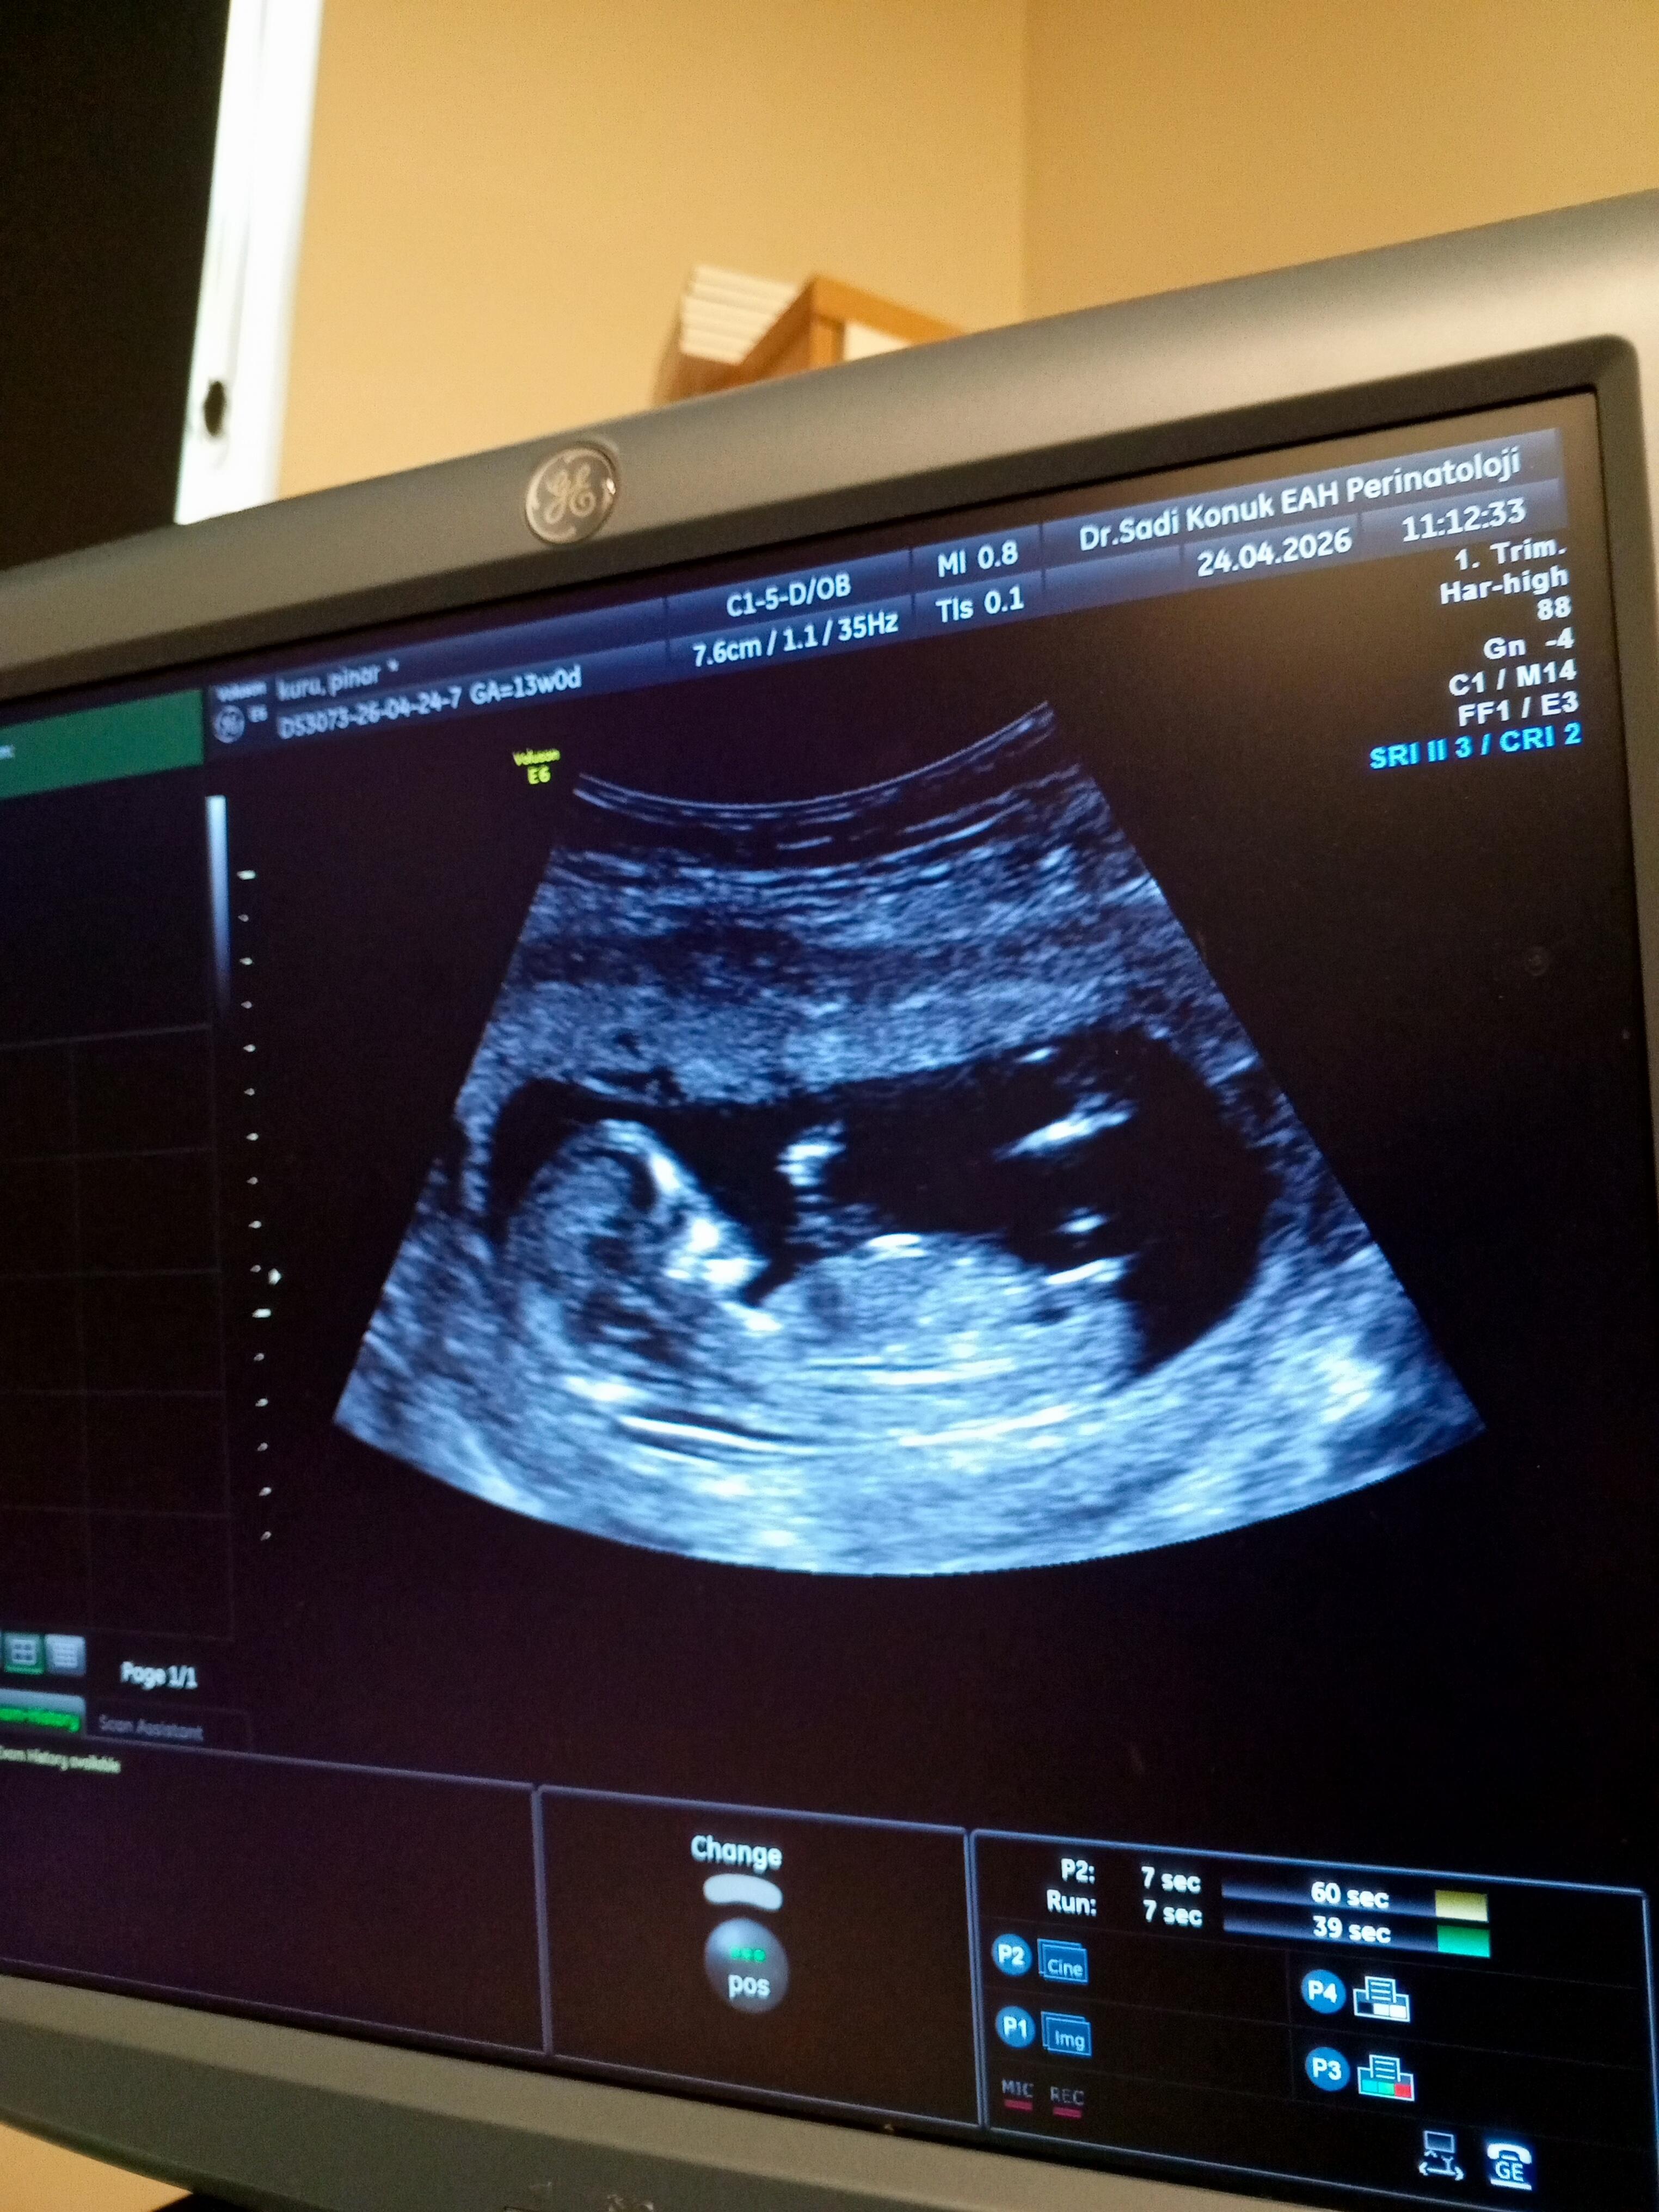

yeni fotografla geldim cinsiyet tahmini alabilirmiyim

@Leyla1991 Güzel anneler sizdende bekliyorum tahmin

Bu attığımda yeni onada bi bakarmısın cnmm